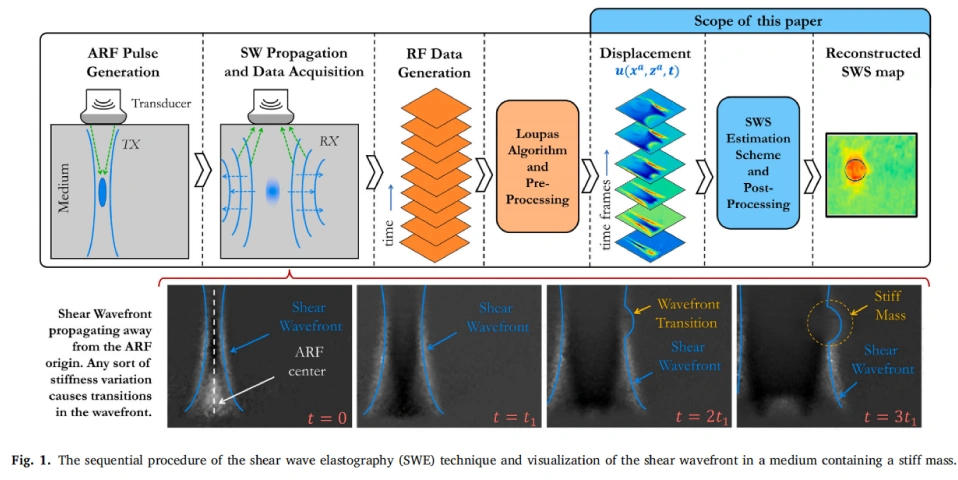

এই কারণেই তৈরি হয়েছে একটি বিশেষ পদ্ধতি যার নাম Shear Wave Elastography (SWE)। এই পদ্ধতিতে একধরনের ক্ষুদ্র কম্পন বা shear wave শরীরের ভেতরে পাঠানো হয়। এই তরঙ্গ পাশের দিকে ছড়িয়ে পড়ে এবং তার গতি (shear wave speed) থেকে বোঝা যায় টিস্যুটি কতটা শক্ত বা নরম। তরঙ্গ যত দ্রুত যাবে, টিস্যু তত শক্ত—এটাই মূল ধারণা।

যদিও SWE প্রযুক্তি খুব কার্যকর, তবুও এতে কিছু বড় সমস্যা ছিল। যখন শরীরের ভেতরে শব্দ তরঙ্গ পাঠানো হয়, তখন সেটি অনেক জায়গায় প্রতিফলিত হয় বা মিশে যায়, যার ফলে noise তৈরি হয়—মানে ভুল বা অপ্রয়োজনীয় সিগন্যাল।

এই নয়েজ বা প্রতিফলন তরঙ্গের সঠিক গতি মাপতে বাধা দেয়। অনেক সময় কম্পিউটার ভুল করে ধরে নেয় কোনো মিথ্যা সিগন্যালই আসল তরঙ্গ, ফলে ভুল ফলাফল পাওয়া যায়।

এই সমস্যাগুলো দূর করার জন্য জাহিন আলম তাঁর স্নাতকোত্তর গবেষণায় তৈরি করেছেন এক নতুন গণিত-ভিত্তিক পদ্ধতি, যার নাম Constrained Optimization ভিত্তিক Shear Wave Speed Estimation।

সহজভাবে বললে, এই পদ্ধতিতে কম্পিউটার শুধুমাত্র এক জায়গার ডেটা না দেখে, পাশের অঞ্চলগুলোর ডেটাও একসাথে বিশ্লেষণ করে। এতে করে যদি কোনো অংশে নয়েজ বা বিকৃতি থাকে, পাশের তথ্য তা ঠিক করে দেয়। ফলে ফলাফল হয় অনেক বেশি নির্ভুল ও স্থিতিশীল।

এই পদ্ধতিতে তিনি আরও একটি নতুন ধাপ যোগ করেছেন—Time-Lateral Plane Cleaning। এটি এমন একটি প্রক্রিয়া, যা SWE ডেটা থেকে মিথ্যা সিগন্যাল বা প্রতিফলন সরিয়ে দেয়। ফলে শুধু আসল তরঙ্গের তথ্যই বিশ্লেষণে ব্যবহৃত হয়।

এইভাবে তাঁর তৈরি সিস্টেমটি noise-resistant, অর্থাৎ নয়েজ বা প্রতিধ্বনির প্রভাব থেকে অনেক বেশি সুরক্ষিত।

এটি তৈরি করে একদম পরিষ্কার stiffness map, যা চিকিৎসকদের শরীরের ভেতরের কঠিন ও নরম অংশগুলো সহজে আলাদা করতে সাহায্য করে।